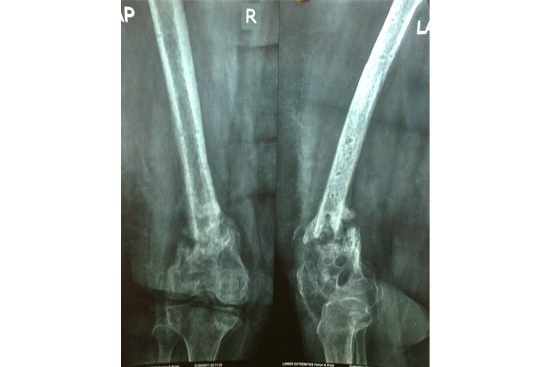

Non Union Femur

Case 2 (Rampyari)